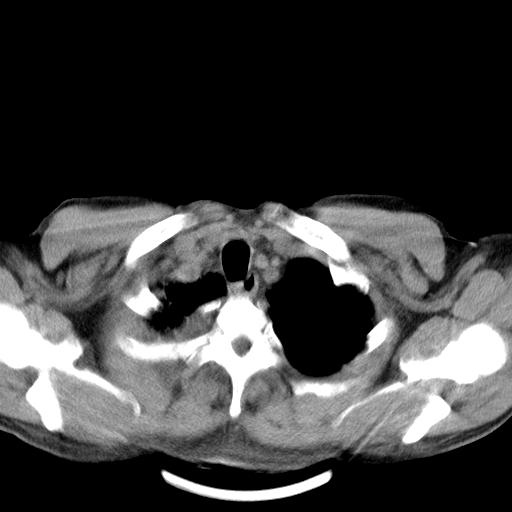

以下是引用zjzjr在2010-3-21 17:39:00的发言:[br]右下中心型肺癌并阻塞性肺炎/不张,纵膈淋巴结肿大,右侧大量胸腔积液,左侧少量胸腔积液

以下是引用zxl51642在2010-3-21 17:06:00的发言:[br]右下中心型肺癌并阻塞性肺炎/不张,纵膈淋巴结肿大,右侧大量胸腔积液,左侧少量胸腔积液,少量腹水。建议纤维支气管镜进一步检查。